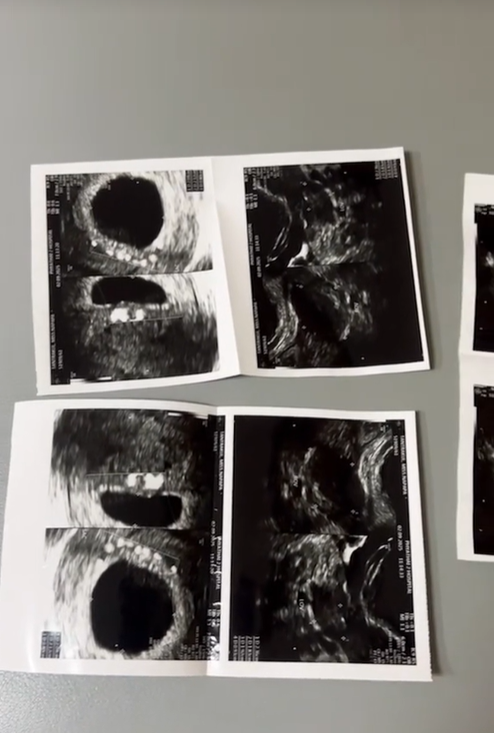

ล่าสุดเนื่องในโอกาสวันคล้ายวันเกิดของแฟนหนุ่ม “พี ชานนท์” งานนี้ “แพท” ได้เตรียมเซอร์ไพรส์ใหญ่ให้เป็นที่ตรวจครรภ์ที่แสดงผล 2 ขีด ทำเอาหนุ่ม “พี” ดีใจยกใหญ่จนพากันไปอัลตร้าซาวน์กับคุณหมอ

แต่เมื่ออัลตร้าซาวน์ดูแล้วคุณหมอบอกว่าเป็นการท้องลมเพียงเท่านั้น ถึงแม้ครั้งนี้เบบี๋จะยังไม่มาสาว “แพท” ก็ยังไม่ลดละความพยายาม รอลุ้นกันใหม่ ทางด้านแฟนคลับก็ส่งกำลังใจให้อย่างมากมาย